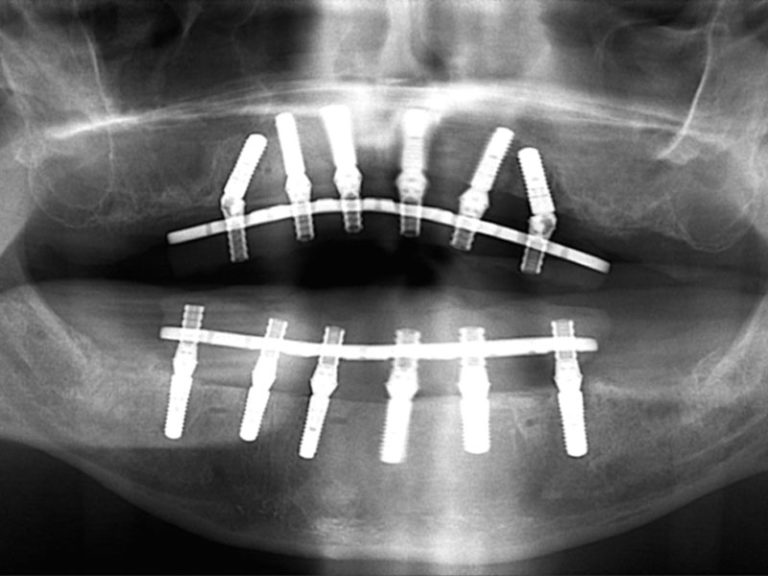

- Implant-supported dentures – Attach to implants for better stability.

Full dentures rely on suction and adhesives, while partial dentures attach to remaining teeth with clasps. Implant-supported dentures provide maximum stability without slipping.

- Implant-supported dentures: $15,000 – $30,000 per arch